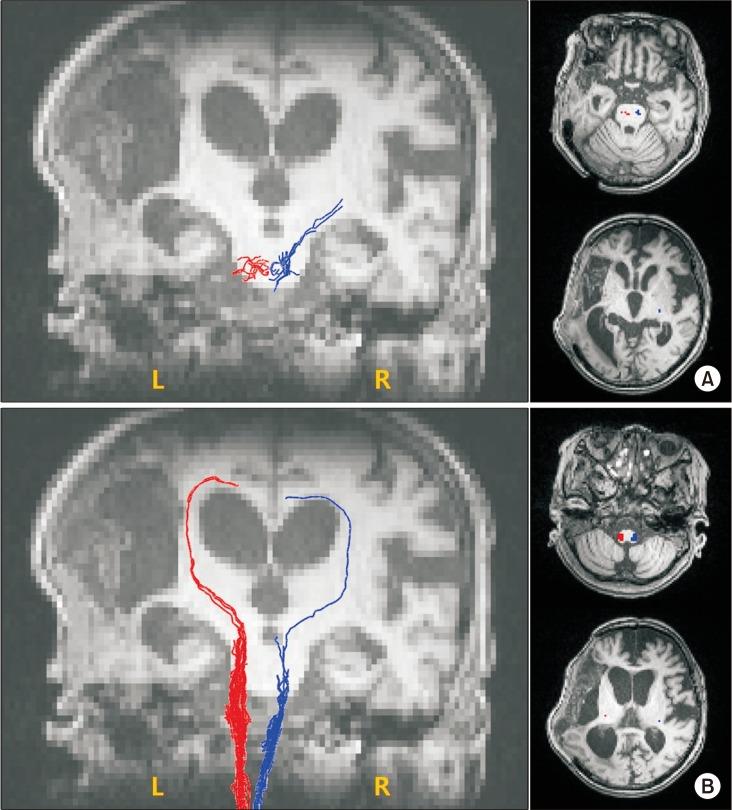

Complex regional pain syndrome (CRPS) type I in stroke patients is usually known to affect the hemiplegic upper limb. We report a case of CRPS presented in an ipsilesional arm of a 72-year-old female patient after an ischemic stroke at the left middle cerebral artery territory. Clinical signs such as painful range of motion and hyperalgesia of her left upper extremity, swollen left hand, and dystonic posture were suggestive of CRPS. A three-phase bone scintigraphy showed increased uptake in all phases in the ipsilesional arm. Diffusion tensor tractography showed significantly decreased fiber numbers of the corticospinal tract and the spinothalamic tract in both unaffected and affected hemispheres. Pain and range of motion of the left arm of the patient improved after oral steroids with a starting dose of 50 mg/day.

复杂区域疼痛综合征(CRPS)I型在中风患者中通常已知会影响偏瘫上肢。我们报告一例CRPS病例,发生在一名72岁女性患者左侧大脑中动脉区域缺血性中风后的同侧手臂。临床体征,如左侧上肢活动时疼痛和痛觉过敏、左手肿胀以及肌张力障碍姿势,提示为CRPS。三相骨闪烁显像显示同侧手臂各期摄取均增加。弥散张量纤维束成像显示,在未受影响和受影响的半球中,皮质脊髓束和脊髓丘脑束的纤维数量均显著减少。患者口服起始剂量为50 mg/天的类固醇后,左臂疼痛和活动范围得到改善。